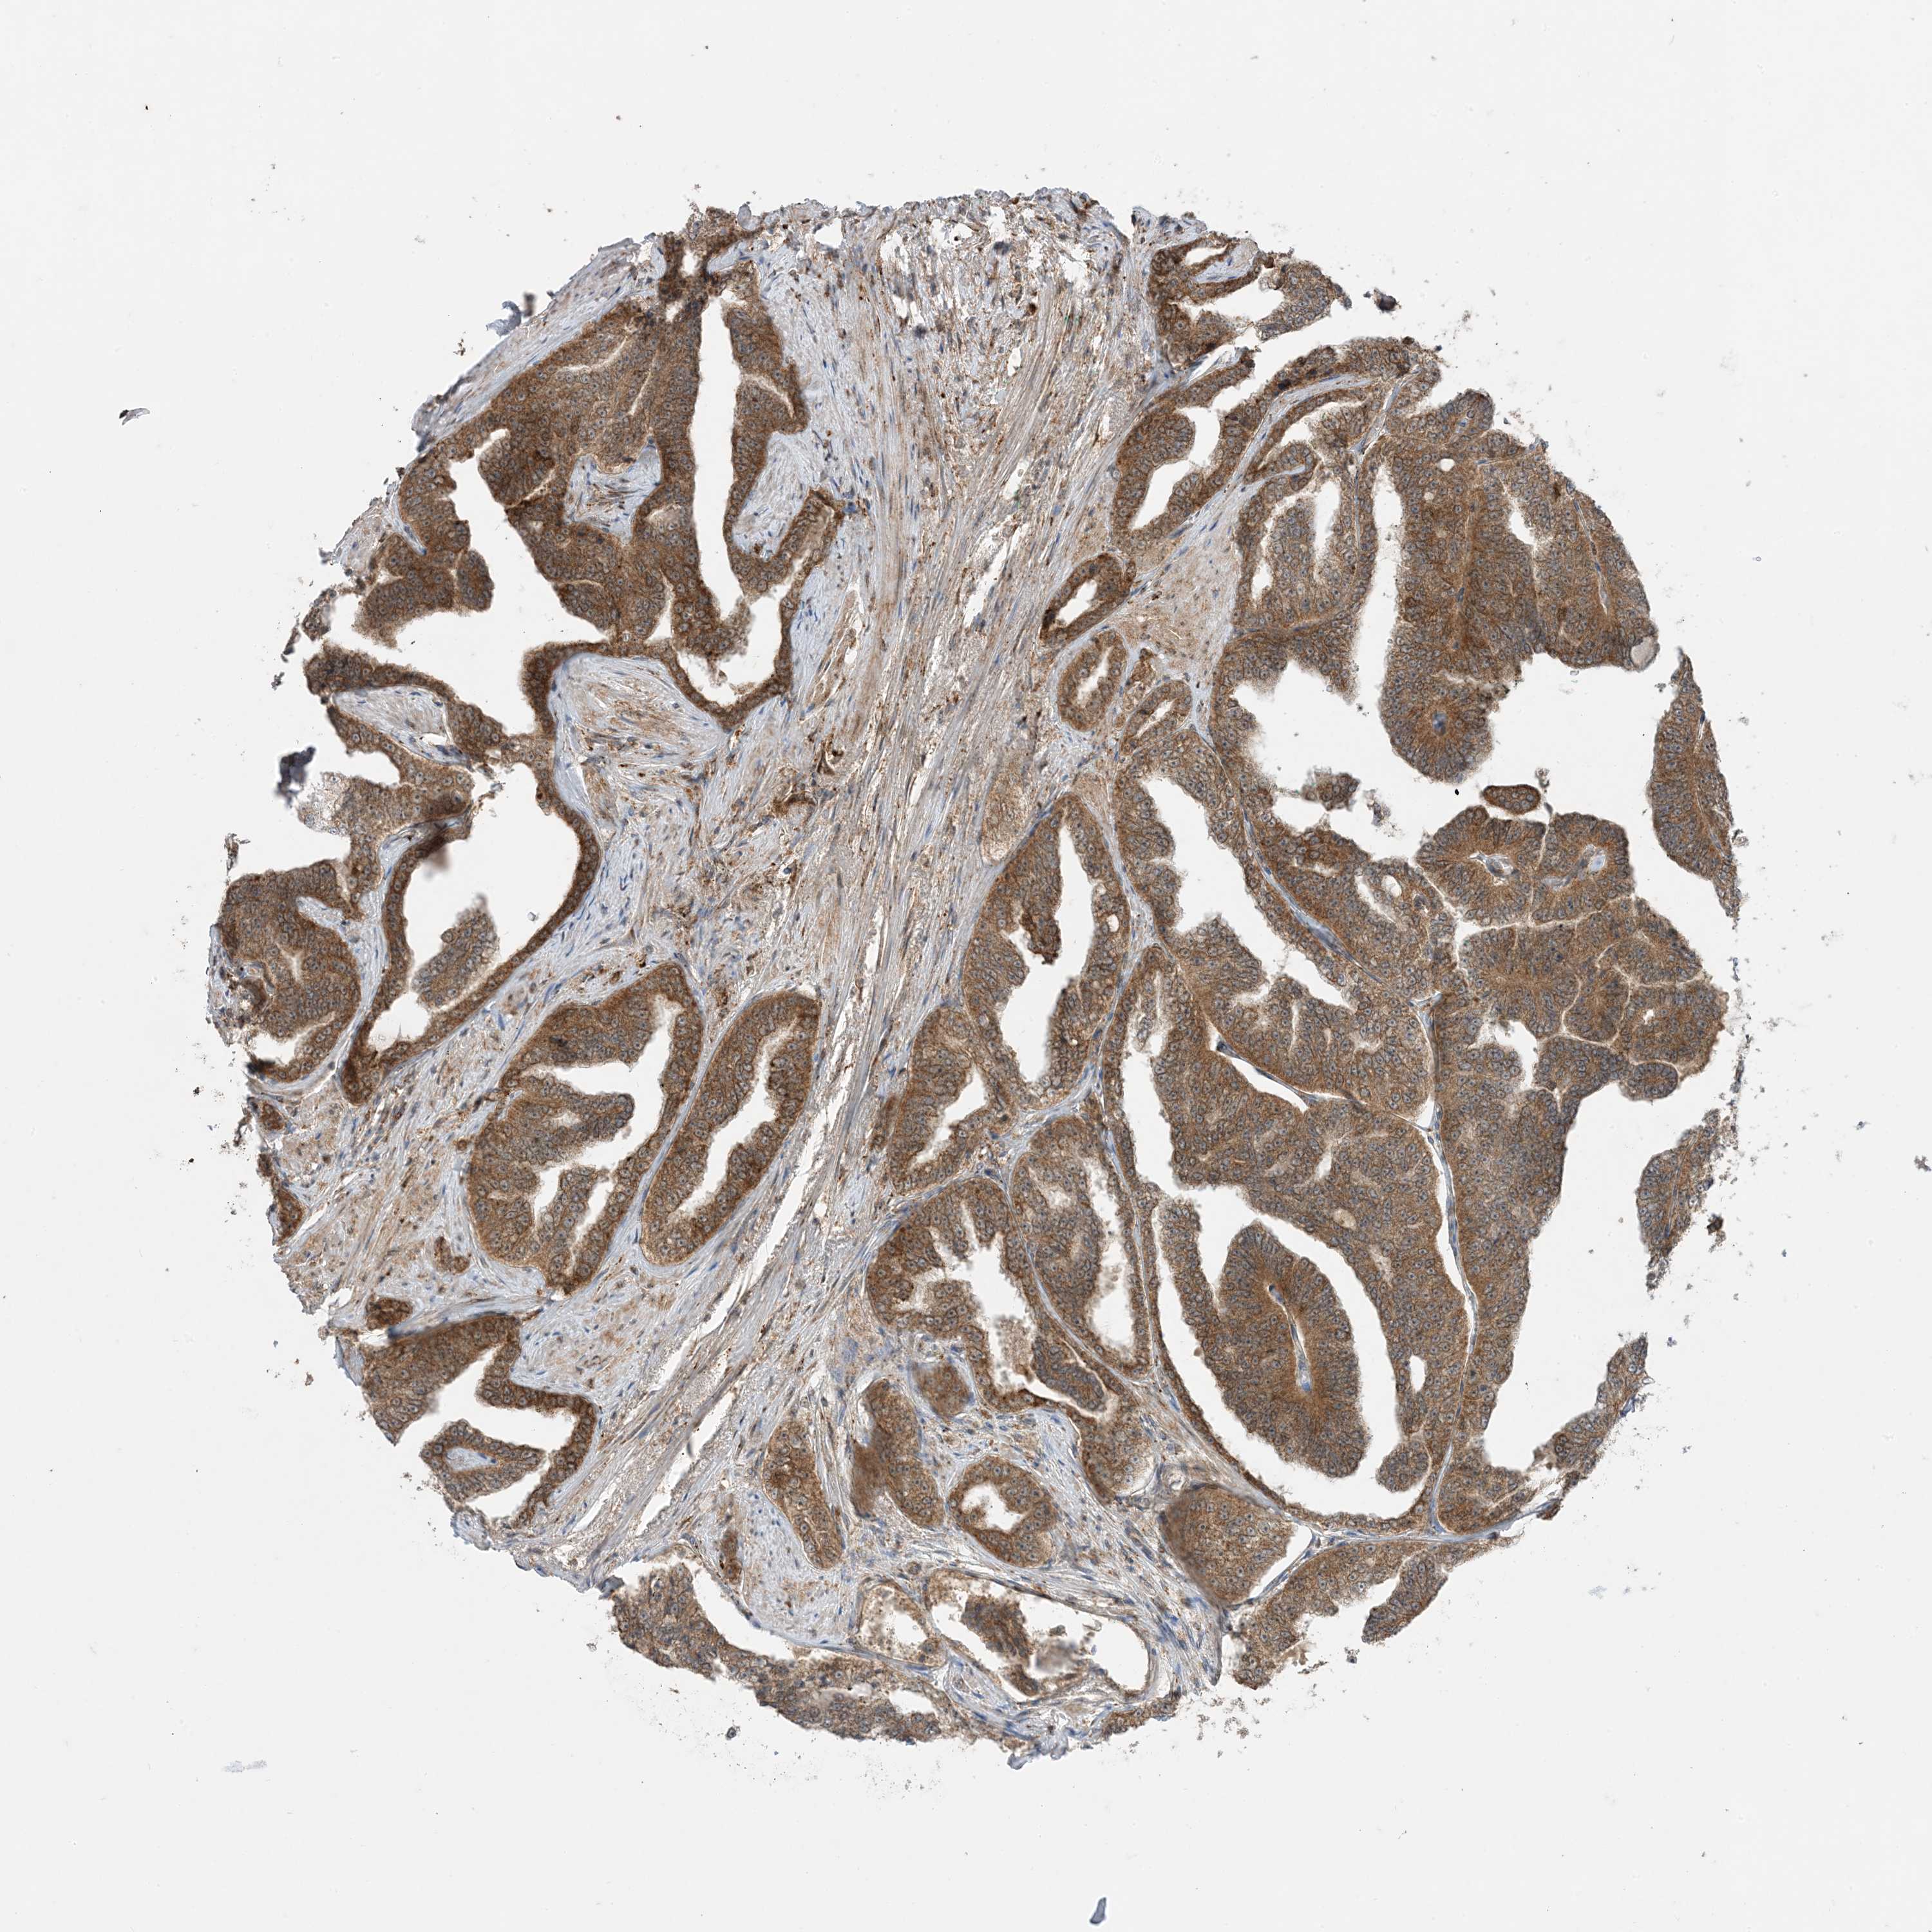

PROSTATE CANCER - Protein expressioni

A mouse-over function shows sample information and annotation data. Click on an image to view it in a full screen mode. Samples can be filtered based on level of antibody staining by selecting one or several of the following categories: high, medium, low and not detected. The assay and annotation is described here.

Note that samples used for immunohistochemistry by the Human Protein Atlas do not correspond to samples in the TCGA dataset.

Antibody stainingi

Antibody staining in the annotated cell types in the current human tissue is reported as not detected, low, medium, or high, based on conventional immunohistochemistry profiling in selected tissues. This score is based on the combination of the staining intensity and fraction of stained cells.

Each image is clickable and will lead to virtual microscopy that enables deeper exploration of all samples and also displays staining intensity scores, fraction scores and subcellular localization as well as patient and tissue information for each sample.

Antibody HPA001536

Antibody CAB035996

Staining

High

Medium

Low

Not detected

Intensity

Strong

Moderate

Weak

Negative

Quantity

>75%

75%-25%

<25%

None

Location

Nuclear

Cytoplasmic/membranous

Cytoplasmic/membranous,nuclear

Adenocarcinoma, Medium grade

Adenocarcinoma, High grade

Adenocarcinoma, Low grade